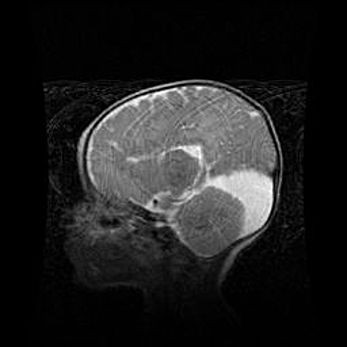

Множественные кисты обоих полушарий головного мозга, наибольшая из них в правой затылочной области. Ассиметричная атрофическая гидроцефалия.

Возраст: 7 месяцев

Вес: 5660 г

Пол: мужской

Окружность головы: 41,5 см

Срок гестации: 28-29 недель

Кисты головного мозга развиваются в результате многоочаговых некрозов вещества мозга и возникают вследствие перенесенной перинатальной инфекции, менингитов, энцефалитов, асфиксии, родовой травмы, расстройств мозгового кровообращения различного генеза. Образованию кист в веществе головного мозга плодов и новорожденных способствуют такие факторы, как высокое содержание в нем воды, недостаточная (или отсутствие) миелинизация и слабая астроглиальная реакция на повреждение.

Кисты могут сочетаться с гидроцефалией и другими поражениями головного мозга.